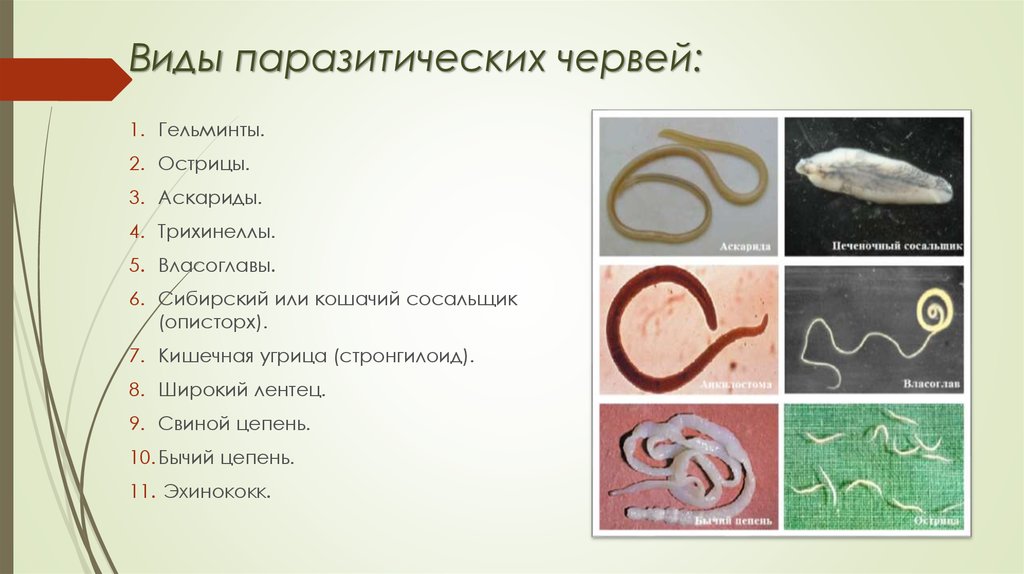

Фотографии нематод, цестод и трематод в природе

Раздел: Другие животные